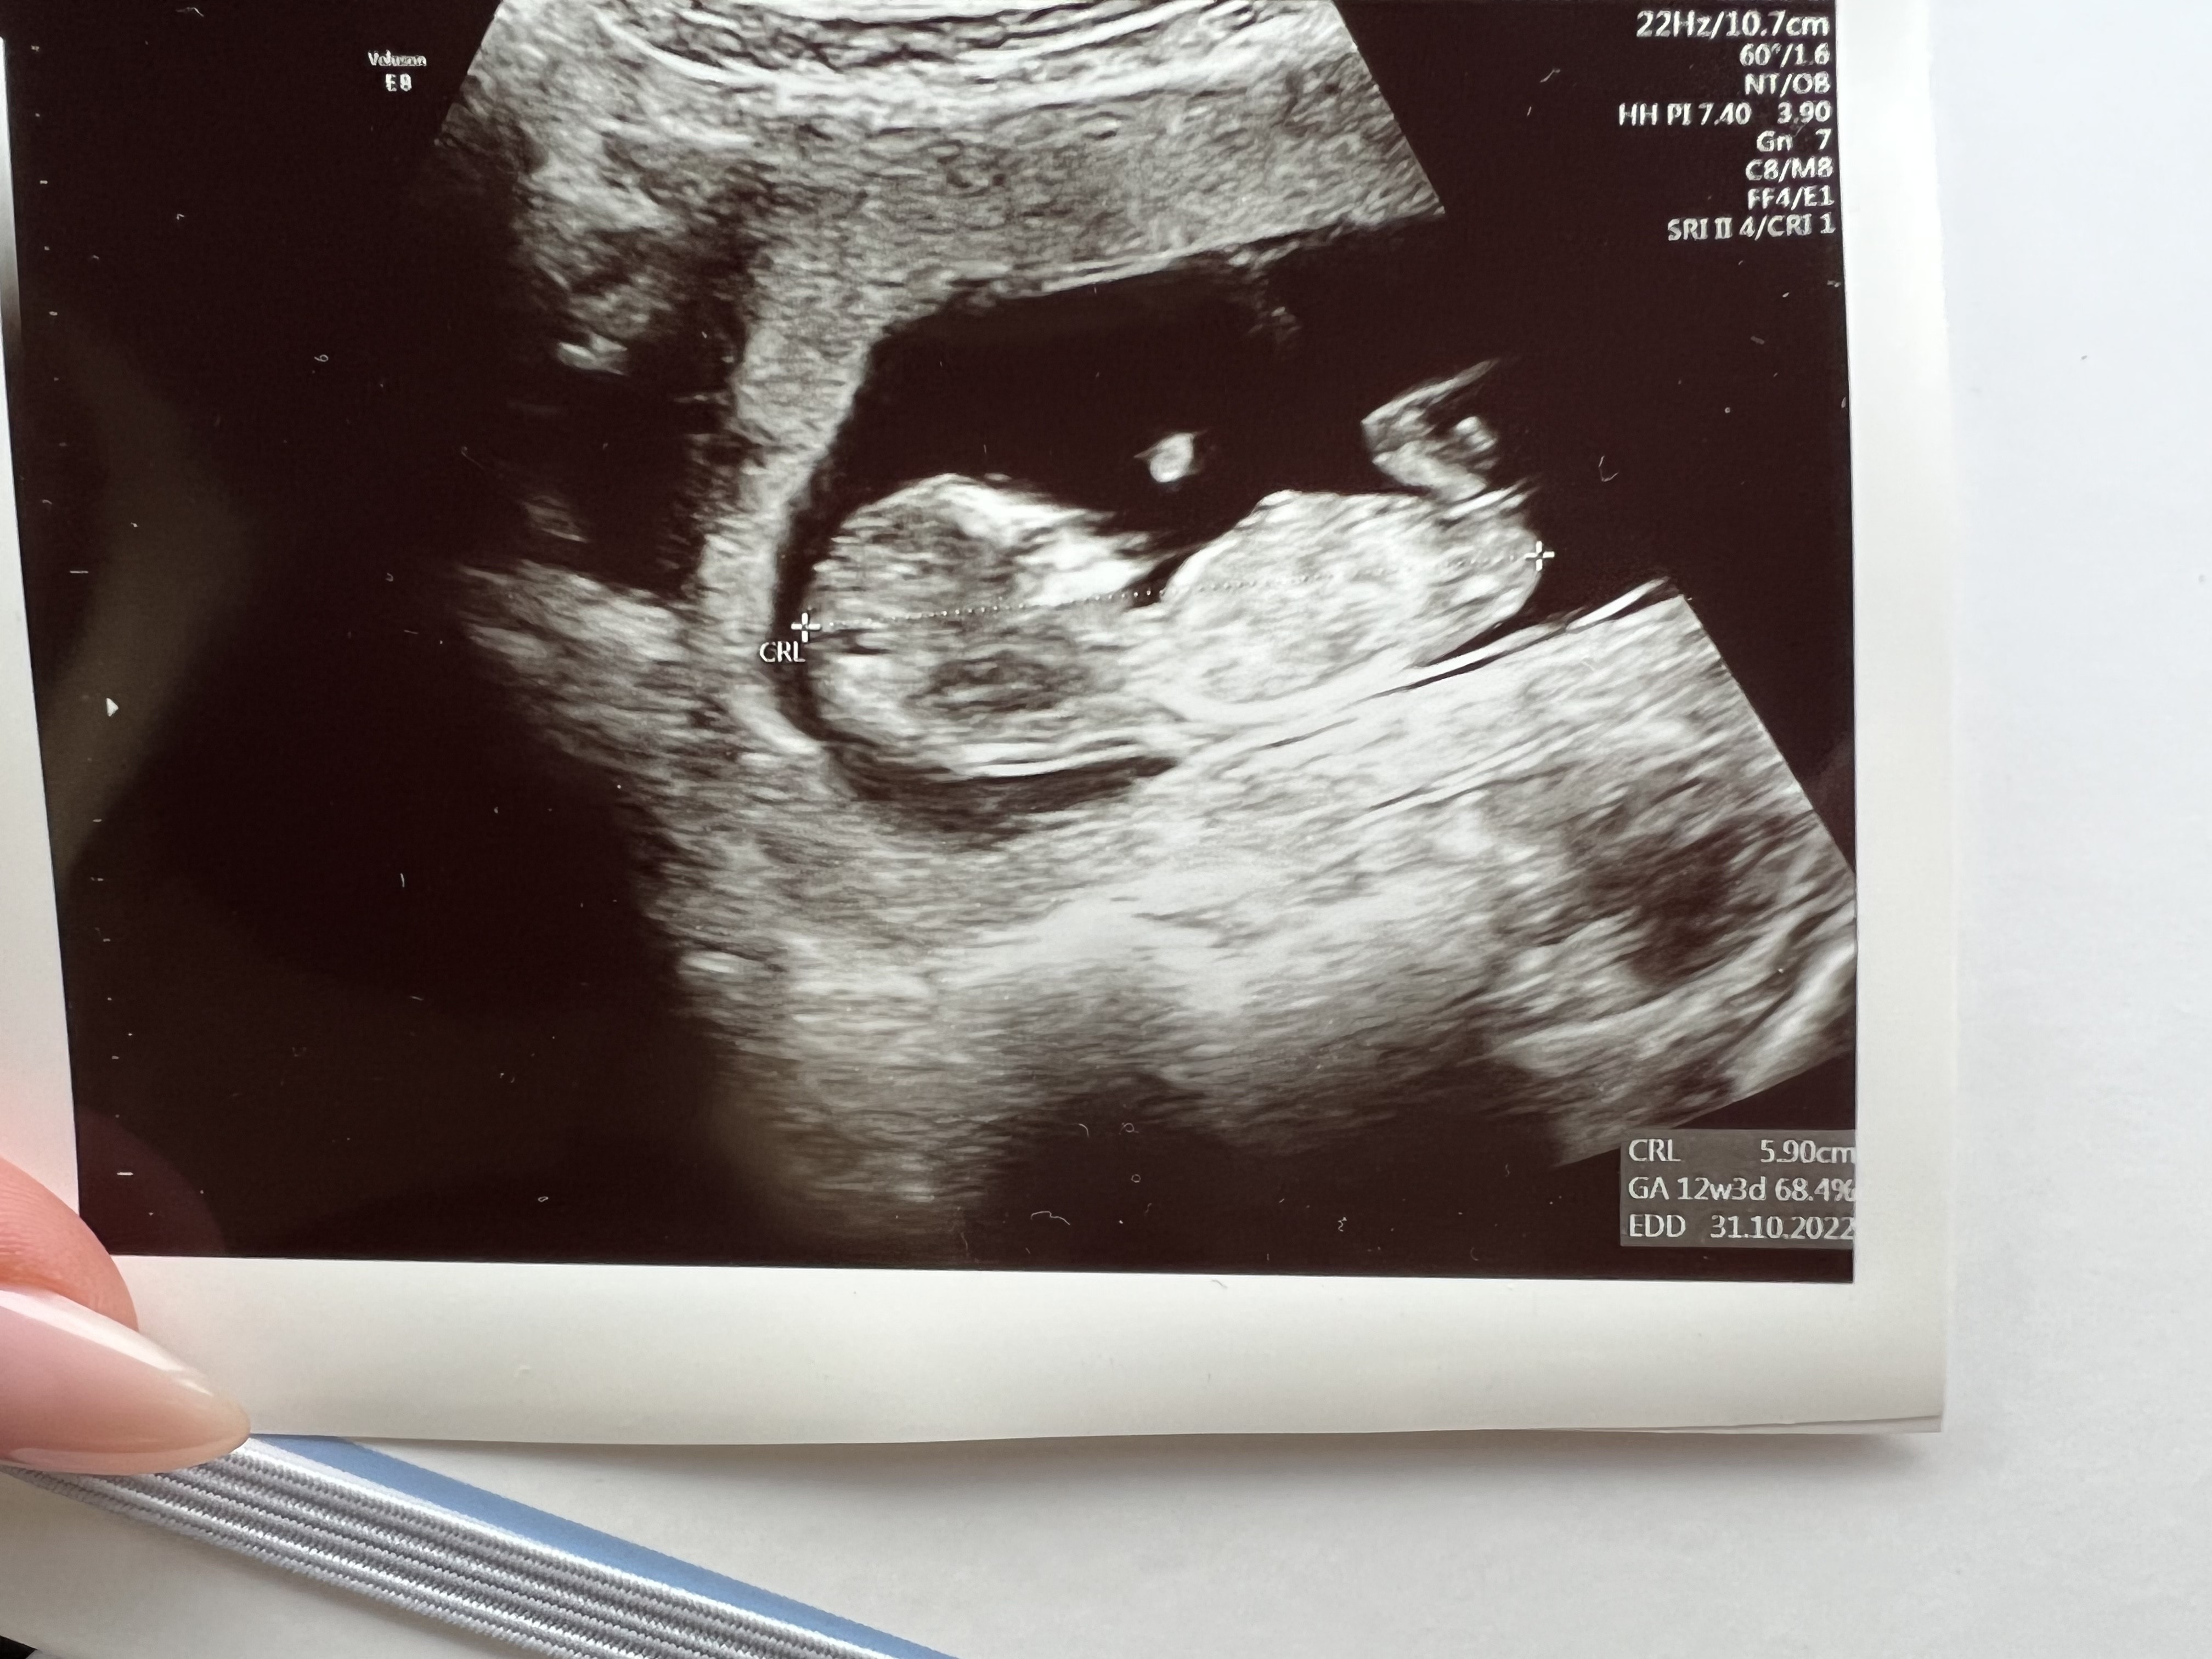

Wlasnie wyszlam, okazalo sie, ze jak zwykle nie bylo sie czym stresowac. Dzidzia jest zdrowa, nawet nam machala podczas USG😁

Ryzyka sa minimalne, 1:20000

Jestem przeszczesliwa!

Załączniki

• 645F929F-2503-4F04-9A48-5E1D21D35970.jpeg

645F929F-2503-4F04-9A48-5E1D21D35970.jpeg

1,4 MB · Wyświetleń: 86